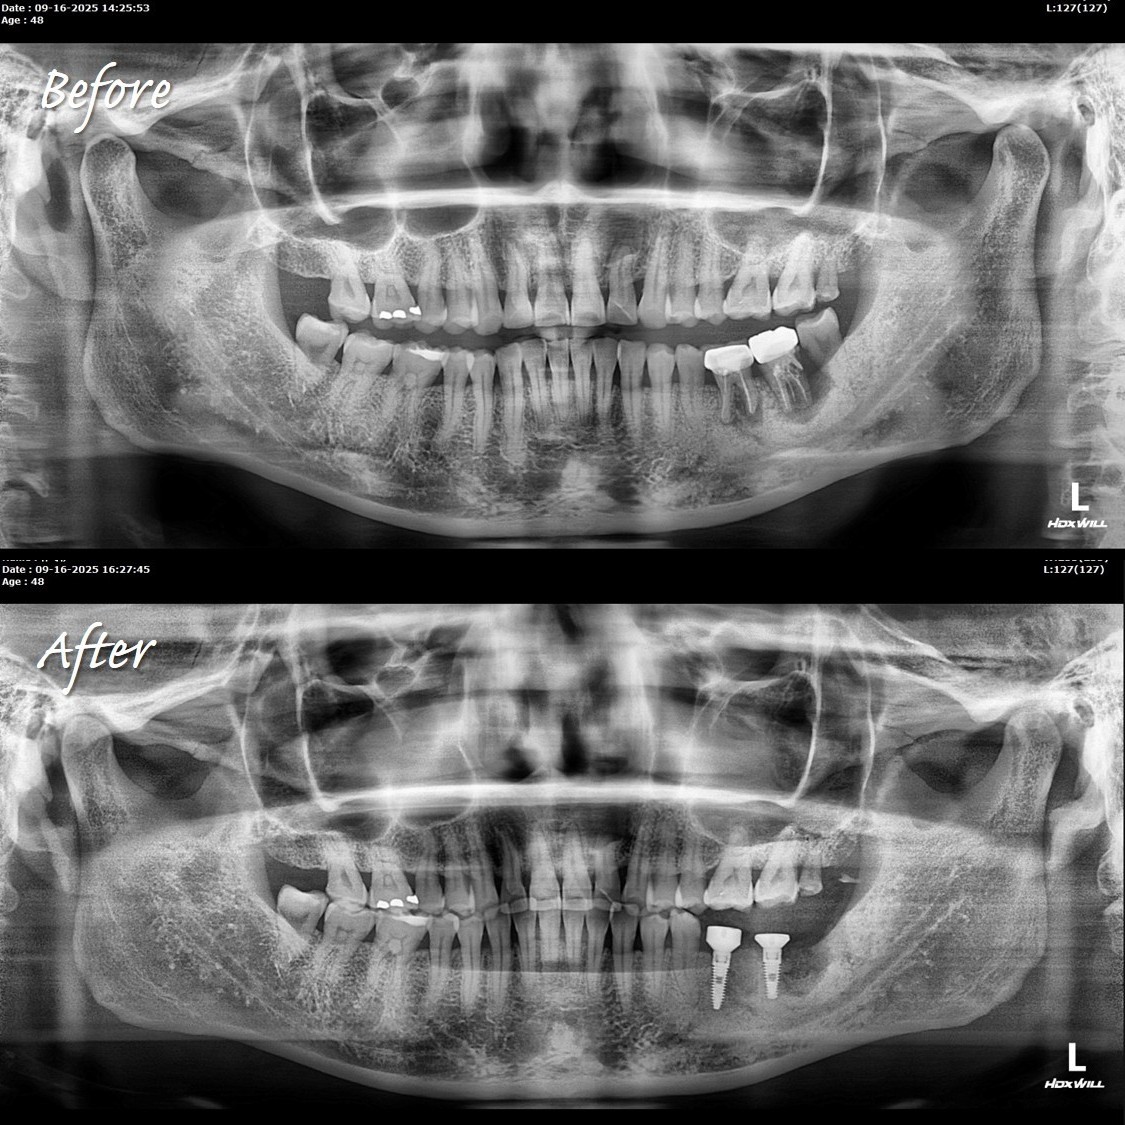

陳俊龍博士分享,診所傳來X光片,讓他疑惑自己沒上班,怎麼會有植牙案例。

仔細一看才知道,原來是年輕醫師完成的植牙案例,成果相當漂亮,堪稱完美的植牙案例。

他也只在陳博士身邊學習一兩年,就能做到比「大師」還厲害的案例。從X光片的時間能看出,同一天下午完成即拔即植。

陳博士強調:工具對了、方法正確,就能做到。眼見為憑,成果就是最好的證明。能在短時間內達到這樣的水準,已經非常不容易。

至於有些人會質疑,為什麼植牙角度沒有依循 curve of Spee 或 curve of Wilson?

陳博士強調的理念,與傳統「平行自然牙根」的思維截然不同。

換個角度思考:假如有人堅持植體必須依照 curve of Spee 或 curve of Wilson,那現在廣受推崇的 All-on-X案例,是否也是遵循這些曲線?這樣的角度設計真的正確嗎?能確保五年以上不出問題嗎?

陳博士能自信地說,他的許多案例已經穩定追蹤20至30年以上;而One Drill System也已有17、18年以上的臨床驗證。

綜觀這些長期結果,證明他的觀念經得起時間的考驗。